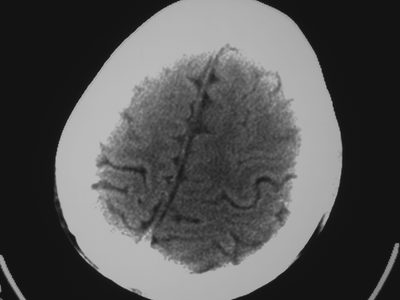

以下是引用卜一在2007-1-19 15:29:00的发言:[br]治疗前:1月14日右侧额叶皮质下低密度影,而治疗后:1月18日右侧阴影消失,新近出现左侧额叶侧脑室前角旁大片状低密度影,边缘模糊。支持—双侧额叶后部缺血性脑梗塞。